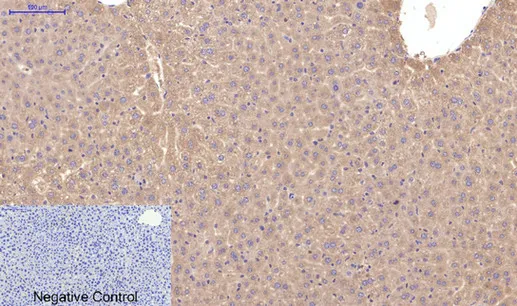

AFP alpha 1 Fetoprotein(17C5)Mouse Monoclonal Antibody

Cat: AMM06666

Size1:50μL Price1:$118

Size2:100μL Price2:$220

Size3:200μL Price3:$380

Application:WB,IHC-P,IF-P,IF-F,ICC/IF

Reactivity:Human

Conjugate:Unconjugated

Optional conjugates: Biotin, FITC (free of charge). See other 26 conjugates.

Gene Name:AFP

Size2:100μL Price2:$220

Size3:200μL Price3:$380

Application:WB,IHC-P,IF-P,IF-F,ICC/IF

Reactivity:Human

Conjugate:Unconjugated

Optional conjugates: Biotin, FITC (free of charge). See other 26 conjugates.

Gene Name:AFP